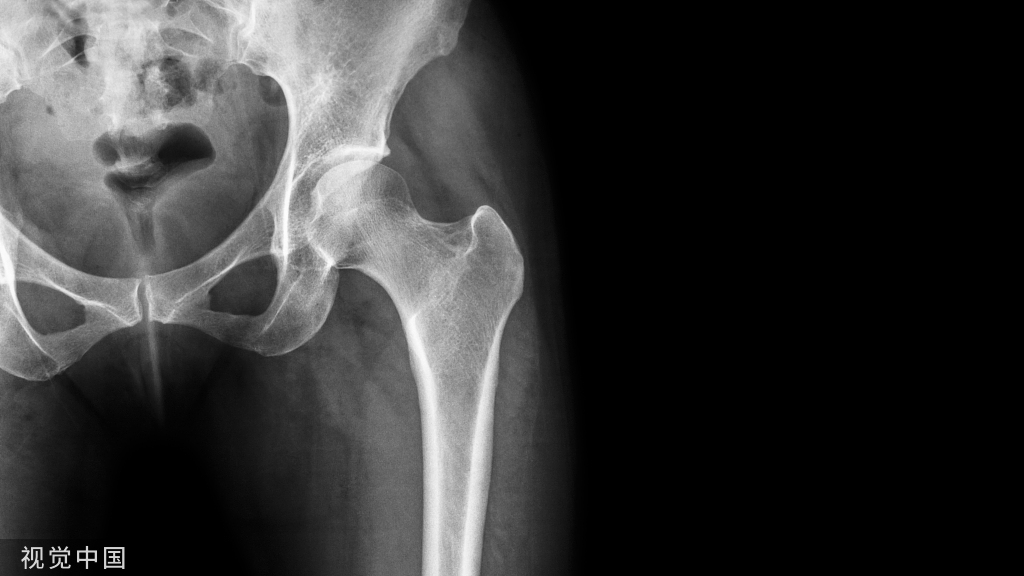

生化标志物在绝经后骨质疏松的治疗中起着重要的疗效评估作用,但它们在糖尿病性骨病中的预测价值目前尚未明确。表3汇总了在糖尿病患者骨折风险评估中具有潜在作用的血清标志物。虽然近年来越来越多的研究发现许多生化标志物与糖尿病骨病的发生发展有关,但迄今为止,最具说服力的糖尿病骨折风险的生物标志物仍然是HbA1c。它体现了一个事实,即控制不良的血糖和复杂的糖尿病病理生理机制是糖尿病患者骨脆性和骨折风险的增加主要决定因素。因此,维持更好的血糖控制,预防微血管并发症的发生,并配合使用对骨细胞活性直接有利的药物(如二甲双胍),是预防糖尿病患者骨质受损的主要途径。

未来的研究仍需要进一步了解生化标志物在糖尿病骨病评价中的作用。具体来说,骨标志物在预测糖尿病骨折风险中的具体作用、敏感性与特异性等问题还需要进一步的研究。到目前为止,只有血糖控制水平和血清IGF-1似乎有可能作为预测糖尿病患者骨折的指标。其他生物标志物尚缺乏与糖尿病骨折直接的相关证据,是未来需要重点阐明的内容。